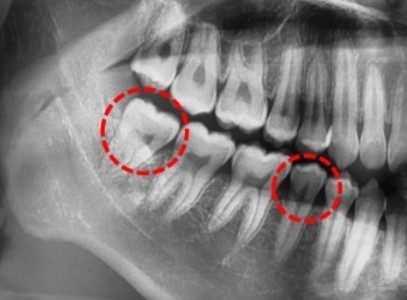

분당 판교 교정치과|10대 여학생 심한 덧니·중심선 편위, 선천적 결손치 발치교정 치료 사례